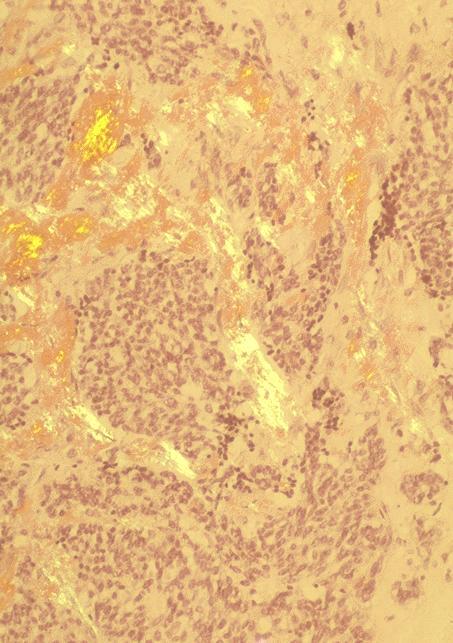

Microscopic (histologic) description

- Wide variety of morphology, can mimic any other thyroid malignancy

- Round, plasmacytoid, polygonal or spindle cells in nests, cords or follicles; often mixtures of these cells

- Round nuclei with finely stippled to coarsely clumped chromatin and indistinct nucleoli, occasional nuclear pseudoinclusion

- Eosinophilic to amphophilic granular cytoplasm due to secretory granules

- Generally low mitotic figures

- Stroma has amyloid deposits from calcitonin, prominent vascularity with glomeruloid configuration or long cords of vessels (Am J Surg Pathol 1995;19:642), coarse calcifications, occasional psammoma-like bodies

- Mucin in 42% (Arch Pathol Lab Med 1983;107:70)

- Often angiolymphatic invasion

- Occasionally marked neutrophilic infiltrate, oncocytic tumor cells, papillary patterns

- May entrap follicles

- C cell hyperplasia present in familial but not sporadic cases

Microscopic (histologic) images

Contributed by Shuanzeng Wei, M.D., Ph.D., Joseph Christopher Castillo, M.D. and Mark R. Wick, M.D.

AFIP images

Images hosted on other servers: